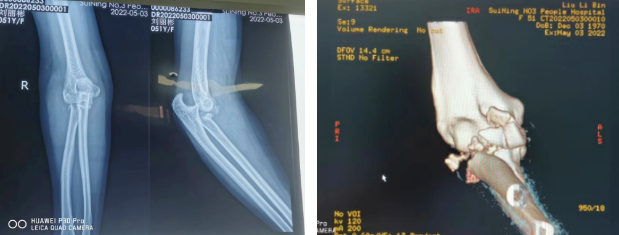

近日,51岁的刘女士不慎摔伤,右肘部损伤严重,外观明显畸形,随即来我院骨伤科就诊,根据CT影像片显示诊断:右侧桡骨头粉碎性骨折、右肘关节脱位。

骨伤科主任医师罗斌为了最大限度地帮助患者改善预后,经科室专家团队讨论,决定为刘女士实施右桡骨头置换手术。